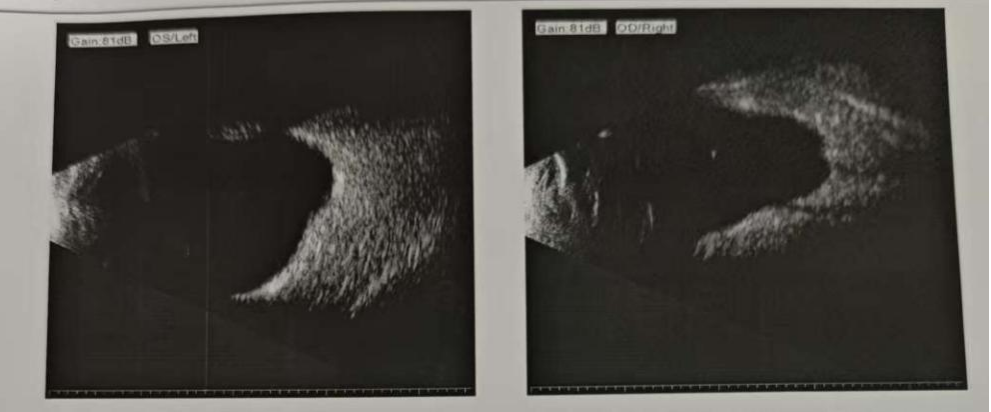

“听说你们这里白内障手术做得特别好,我今天特意过来,看看我还能做手术吗?”一进门,郑阿姨扶了扶脸上那副厚厚的眼镜,语气中透着期盼。多年来,她的世界始终朦胧一片,双眼仅能勉强看见眼前手的晃动。经过详细检查,医生发现她的晶状体已经呈现深棕褐色混浊,眼底情况无法观察,超长眼轴和明显的后巩膜葡萄肿,说明眼球结构已发生显著变化。她感慨道,年轻时从未想过自己是超高度近视,只因当年医疗条件有限,一拖就是几十年。

面对如此复杂的眼部条件,眼科团队联合院外专家进行周密评估,决定为其实施超声乳化白内障手术,并计划在术中植入负度数人工晶体同时矫正近视,一举解决白内障和超高度近视两个问题,帮助郑阿姨远离厚重的镜片。

虽然手术风险不容小觑——超长眼轴让眼球变得“脆弱”,悬韧带松弛、视网膜薄弱等都可能引发并发症,但凭借精准的术前设计和细致的手术操作,团队成功完成了这次高难度手术。术后,郑阿姨的视力获得显著提升,迎来了清晰的新视界。